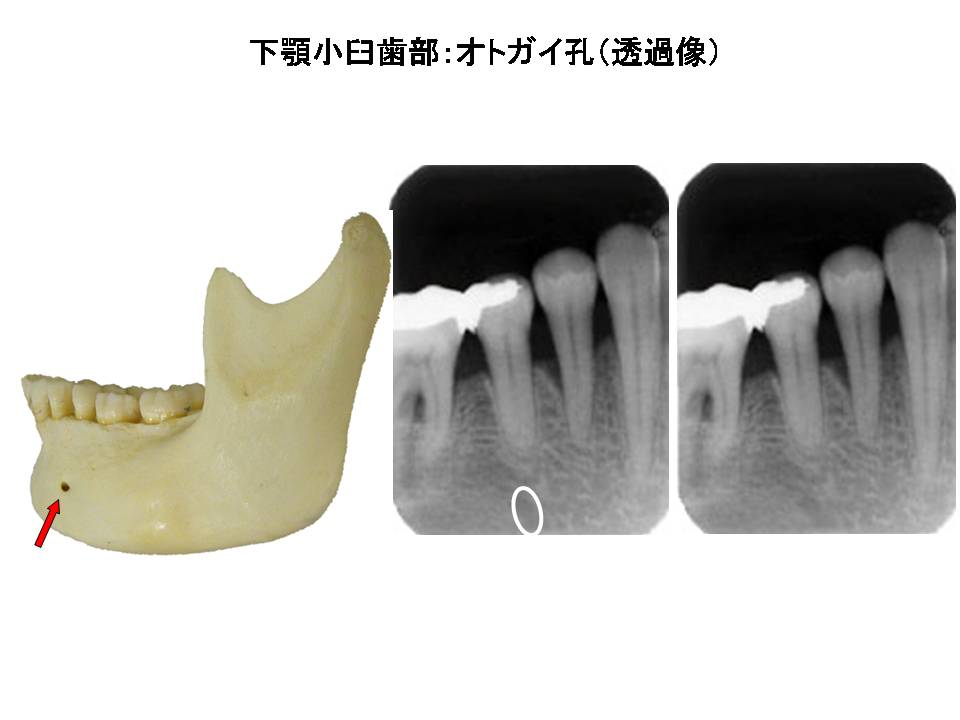

口内法(二等分法・咬合法)撮影の解剖